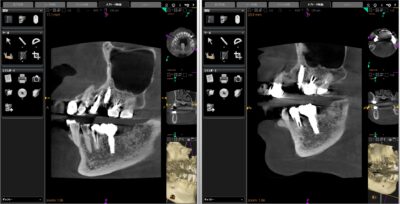

こちらがレントゲンになります

もともと右上にBr.が入っていて手前の第一小臼歯に破折がありました

しばらく様子をみていたのですが、骨吸収が進んでいたので処置を開始することとなりました

まずはポンティックを除去しImplantを埋入➡︎インテグレーション(骨と結合すること)を確認後、型取りをして仮歯を用意➡︎抜歯・GBRの順で処置を行いました

抜いた場所にはImplantは入れずカンチレバー式の上部構造を入れる予定です

◎カンチレバー式とは、1つの片側支台歯で支えられている固定性補綴装置のこと

🦷治療内容:Implant(Nobel Biocare)・GBR・IVS・フルジルコニア(ポンティック)